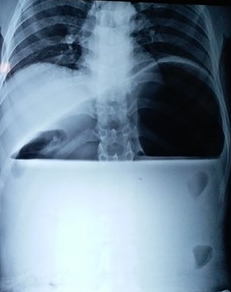

Polycystic liver disease. Red arrow. Infected hepatic cyst (Courtesy Dr. V. Penopoulos)